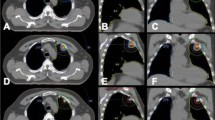

Our treatment methods were described in detail previously [13, 15]. We used the BodyFIX system (Medical Intelligence, Schwabmuenchen, Germany) for patient immobilization. The visible gross tumor volume on CT during three phases (normal breathing and breath holding during the expiratory and inspiratory phases) was superimposed to represent the internal target volume (ITV). Breath-holding-phase CT images were used to ensure the range of tumor motion. During the first study, we had confirmed that a forced inspiration/expiration breath hold would not overestimate the tumor motion and therewith systematically overestimate the margins, by using fluoroscopy [17]. The planning target volume (PTV) margin for the ITV was 5 mm in the lateral and anteroposterior directions and 5–10 mm in the craniocaudal direction. Forward planning was performed using a 3-dimensional treatment planning system (Eclipse Version 7.5.14.3, Varian Medical Systems, Palo Alto, California, USA). Fixed 3 coplanar and 4 non-coplanar beams were used in all cases.

For verification of tumor positions, we used the simulator CT at the first and third treatments in addition to megavoltage portal imaging at every treatment throughout the study period. The patients underwent registration in the CT simulator room, and repositioning was performed whenever necessary. Then, they were carefully transferred to the linac room with a stretcher. SBRT was delivered by CLINAC 23EX (Varian Medical Systems, Palo Alto, California, USA) with 6-MV photon beams and it was delivered with 4 fractions. In principle, the respective fractions were delivered at intervals of ≥ 72 h to allow reoxygenation of hypoxic tumor cells [14], but owing to national holidays, patient schedule convenience, and machine availability, the actual overall treatment period was 8–20 days (median, 11 days). The total dose at the isocenter was increased to 48 Gy for tumors with a maximum diameter < 1.5 cm and 50 Gy for tumors of 1.5–3 cm. For those > 3 cm, the total dose remained at 52 Gy. The dose calculation algorithm was AAA.

It was recommended to cover 95% of the PTV with at least 90% of the isocenter dose, and, in all cases, 95% of the PTV received at least 80% of the prescribed dose. However, the dose was 79.2% in one case. Dose constraints for normal tissues were: (1) volume of the lung receiving 20 Gy, ≤ 20%; (2) 40 Gy for < 1 cm3 of the pulmonary artery and esophagus; (3) 36 Gy for < 10 cm3 of the stomach; and (4) maximum cord dose < 18 Gy, in accordance with the first study [13, 14].